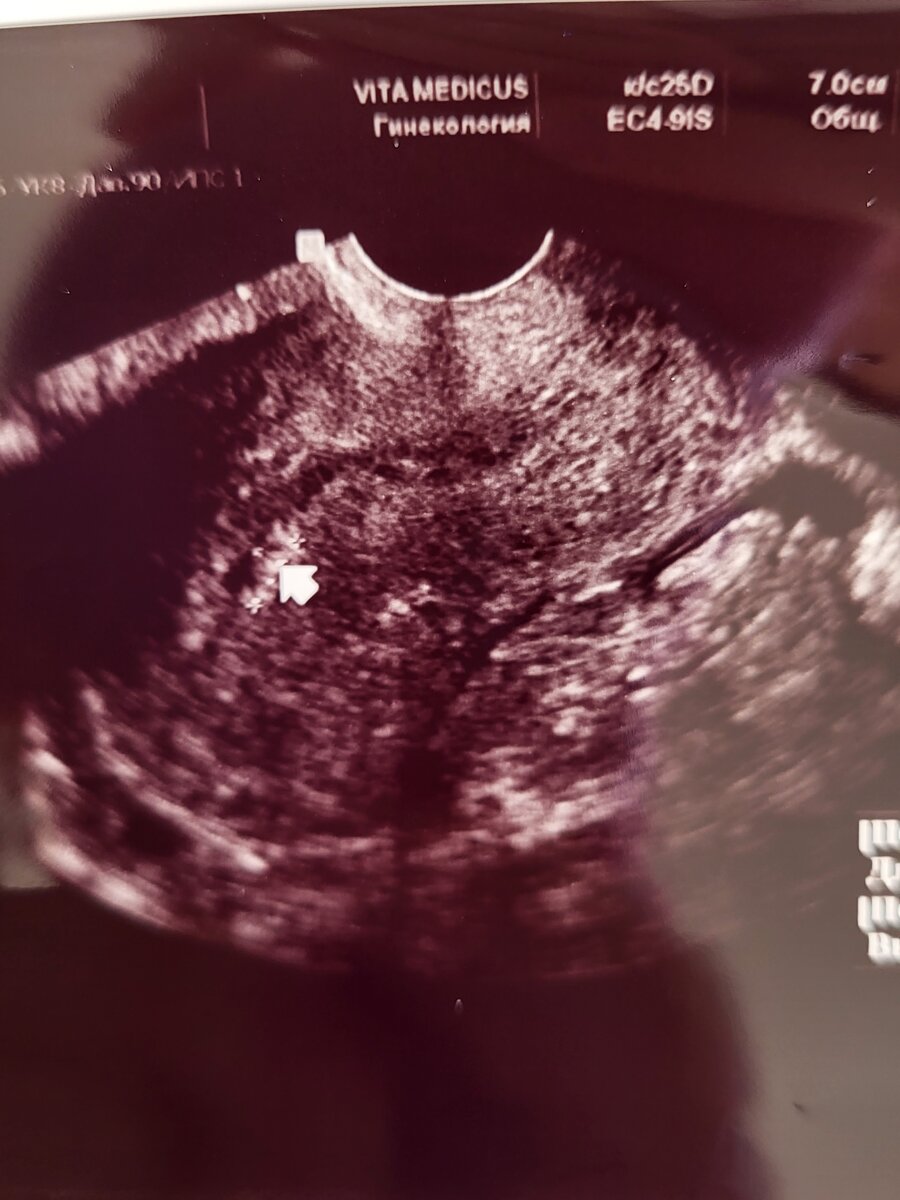

Это мои полипы

Бегу на УЗИ...подозрение на полип эндометрия. Сделали ещё два УЗИ в разные дни цикла куда и вме 3 УЗИ подтвердили наличие полипа. Нужна операция. Чтоооо?! Операция? Да! Операция. Удалять полипы и делать выскабливание...